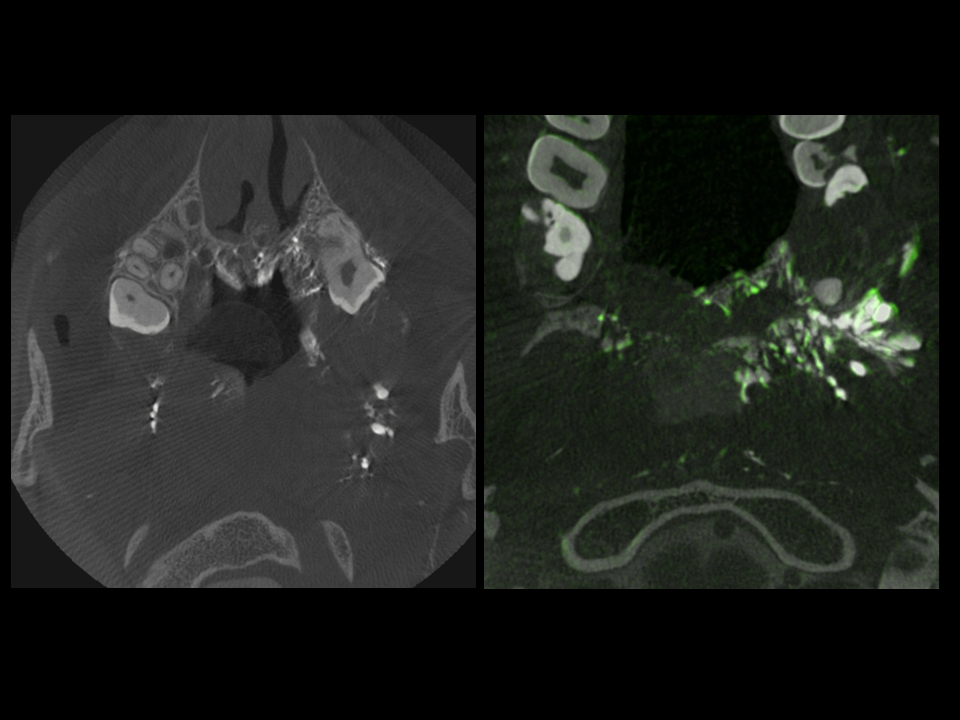

CSF Lymphatic Fistula

A fantastic and unique case